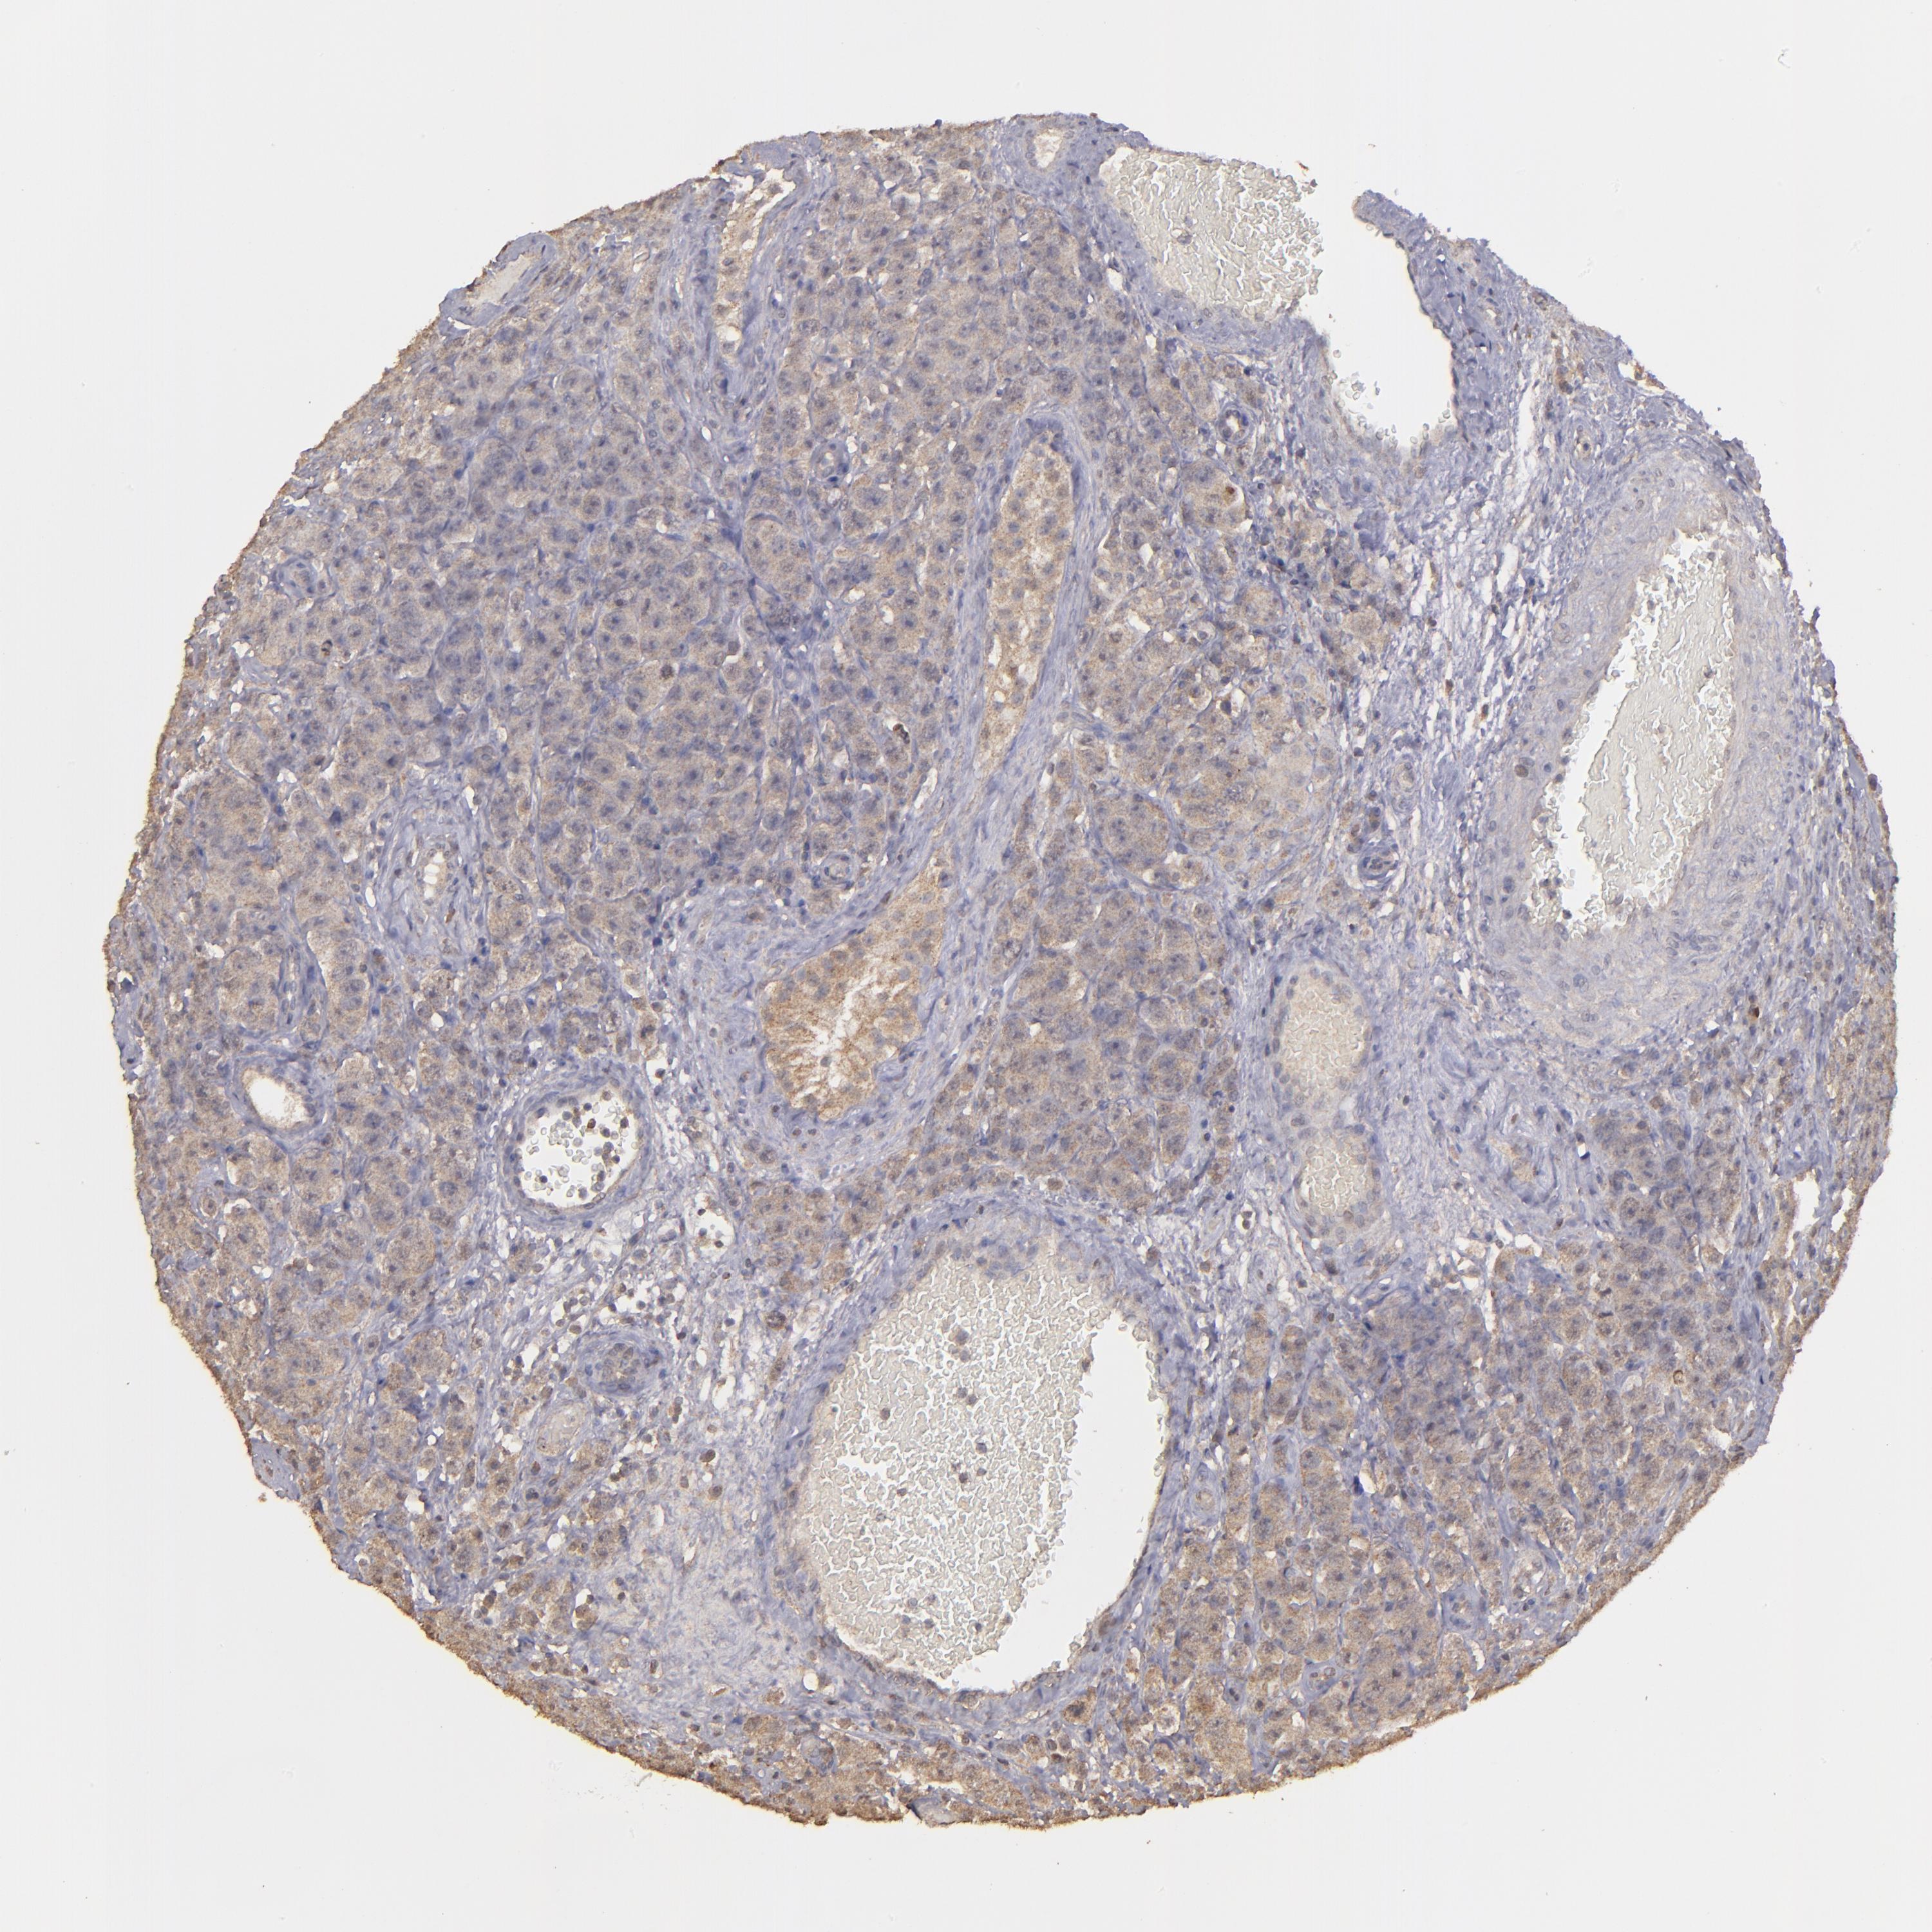

TESTIS CANCER - Protein expressioni

A mouse-over function shows sample information and annotation data. Click on an image to view it in a full screen mode. Samples can be filtered based on level of antibody staining by selecting one or several of the following categories: high, medium, low and not detected. The assay and annotation is described here.

Note that samples used for immunohistochemistry by the Human Protein Atlas do not correspond to samples in the TCGA dataset.

Antibody stainingi

Antibody staining in the annotated cell types in the current human tissue is reported as not detected, low, medium, or high, based on conventional immunohistochemistry profiling in selected tissues. This score is based on the combination of the staining intensity and fraction of stained cells.

Each image is clickable and will lead to virtual microscopy that enables deeper exploration of all samples and also displays staining intensity scores, fraction scores and subcellular localization as well as patient and tissue information for each sample.

Antibody HPA001869

Antibody HPA023882

Staining

High

Medium

Low

Not detected

Intensity

Strong

Moderate

Weak

Negative

Quantity

>75%

75%-25%

<25%

None

Location

Nuclear

Cytoplasmic/membranous

Cytoplasmic/membranous,nuclear

Carcinoma, Embryonal, NOS

Seminoma, NOS